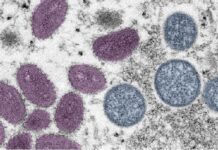

Concern over two cases of monkeypox-related neurological complications in the U.S. – News-Medical.Net

Monkeypox virus (MPXV) is an orthopoxvirus that belongs to the Poxviridae family. The recent multinational outbreak of monkeypox has spread to 96 non-endemic countries. Infections are mostly reported among bisexual, gay, and other...

A second U.S. death was linked to monkeypox on Tuesday as health authorities published a study describing how two previously healthy young men experienced inflammation of the brain and spinal...